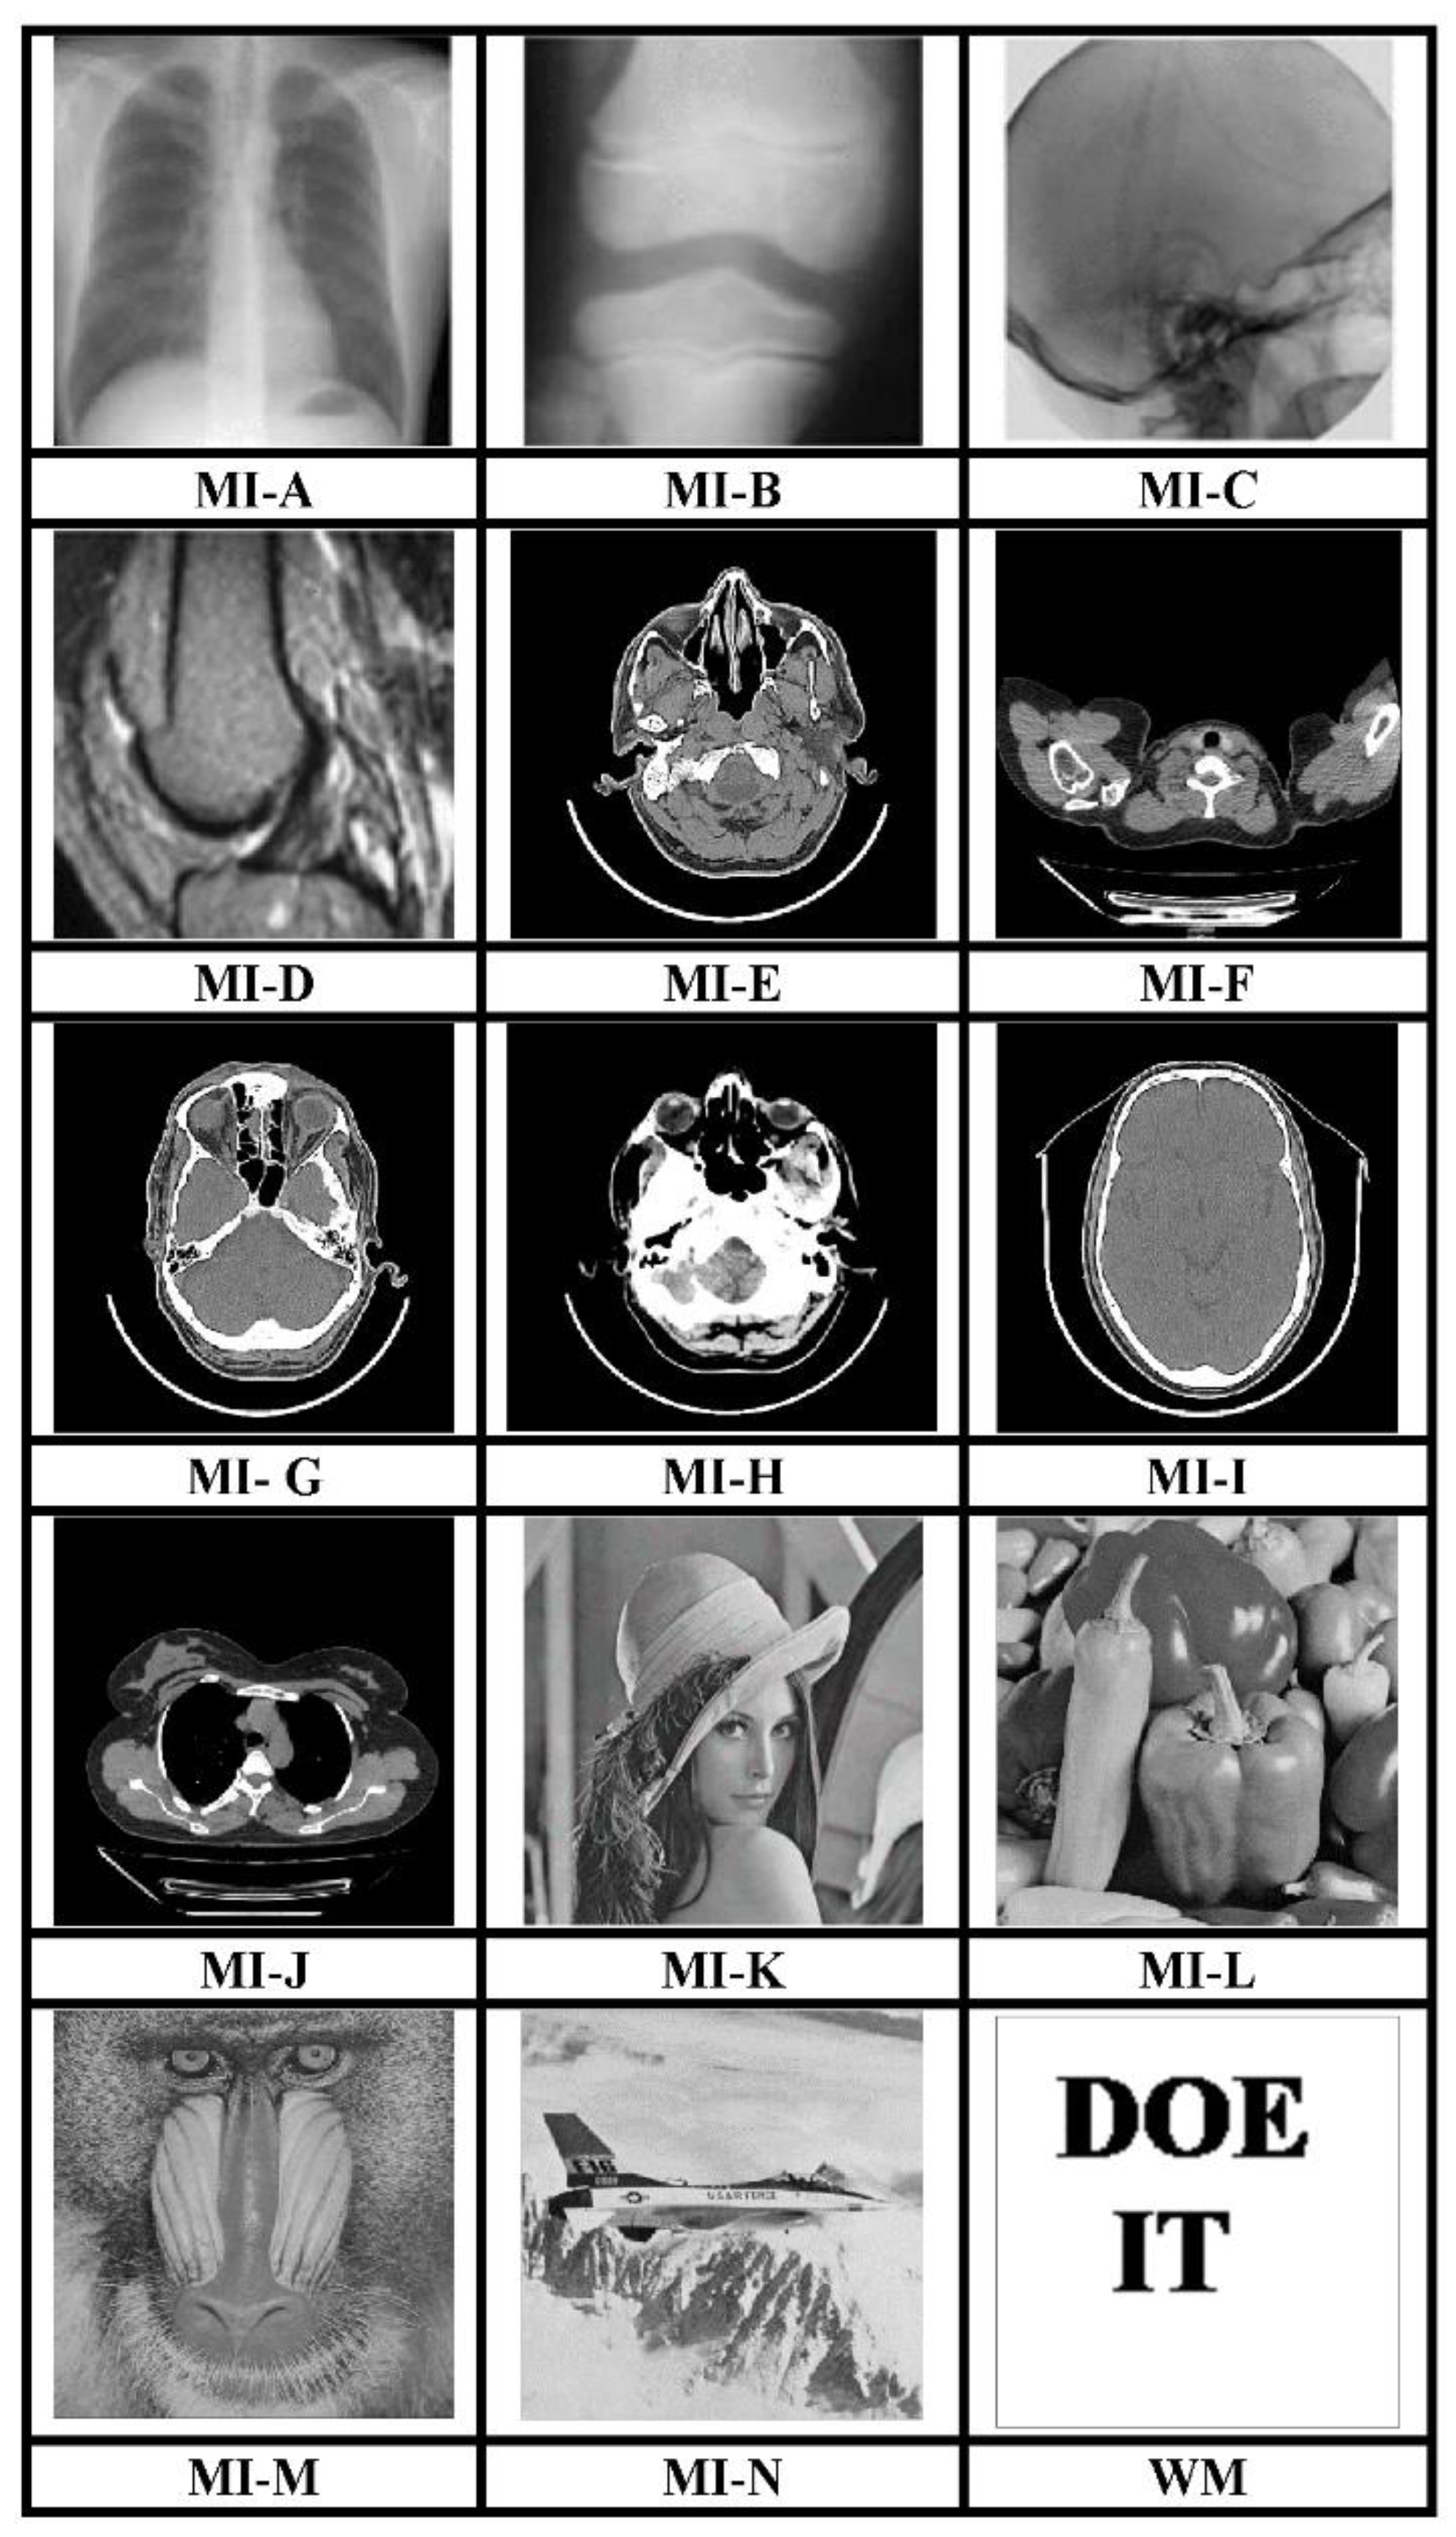

The MATLAB R2017a platform has been utilized for carrying out the experimental investigations for different gray-scale natural and MI. Both types of images that have been used for testing have dimensions 512 × 512. We have conducted experiments using a 64-bit Windows 10 Operating system with an i5 processor, 8 GB RAM, and 2.40 GHz clock speed. The different images, as well as a logo as WM, have been represented in Figure 3. The binary WM employed for authentication purposes has a 128 × 128 size. The technique is evaluated for a payload of 196,608 bits or 0.75 bits per pixel (bpp). The scheme reports an average encryption speed close to 1Mbps. The image quality metrics applied for evaluation of the scheme include normalized cross-correlation (NCC), peak signal to noise Ratio (PSNR), and structural similarity measure index (SSIM) [16,17,18,19,20]. In-depth analysis has been performed, which includes imperceptibility analysis, computational complexity analysis, and fragility analysis. Furthermore, a detailed comparison of many contemporary techniques has been described. Furthermore, the fragility analysis carried out reveals that the WM is fragile to all possible attacks and can easily detect tampering of data.

Figure 3.

512 × 512 test images and 128 × 128 binary WM.

The main attribute of the presented image interpolation method is its capability of generating perceptually better-quality CI. The CIs generated by this scheme are of very high quality as indicated in Figure 4 and the evaluation quality metrics which include the PSNR1 and SSIM1 have been presented in Table 1. The scheme performs equally well for the natural as well as the MI.

Figure 4.

CI (Interpolated).